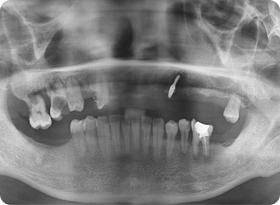

:: 엑스레이 촬영을 통하여 살펴보는 뼈이식 & 임플란트 ::

임플란트 의사 결정

원래라면 저런 어금니 두개가 들어가 있던 자리였죠.

하지만 없으니 임플란트 궈궈!

인공치아 뿌리 식립

이렇게 잇몸뼈 이식술을 통해 인공치아 기둥뿌리를 확실히

심어주는 것입니다!